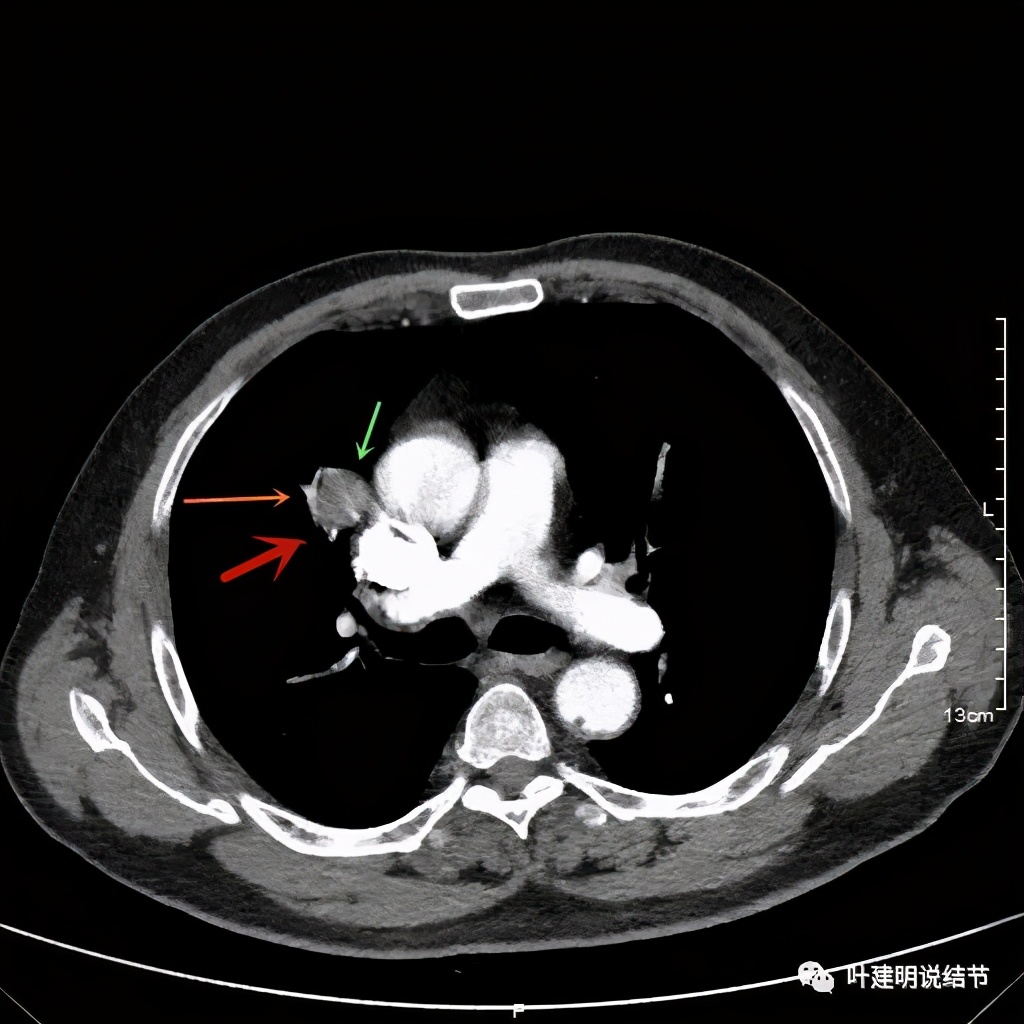

上图示病灶边缘过于光滑(绿色);局部有点状钙化(蓝色)

上图示病灶边缘过于光滑(绿色);血管贴边(桔色);

上图示病灶边缘过于光滑(绿色);血管贴边走行(桔色)

以上几图也示病灶边缘过光(绿色);血管贴边,感觉没受侵犯(桔色)

事前来看,达2.4厘米的不均质实性肿块,增强有轻度不均匀强化,血管贴边走行,支气管疑有截断,恶性不能除外,而且可能性较大。但现在经过手术已已经证实是错构瘤的情况下,我们回头来看,其实有许多不符合恶性的地方:

1、病灶的每个层面,边缘都过于光滑了。肺癌一般到这个大小总要有棘突、分叶、毛刺、牵拉周围胸膜等边缘异常的征象;

2、肿瘤大于2厘米以上,又紧贴血管,多有血管走行异常、受侵或血管进入等征象;